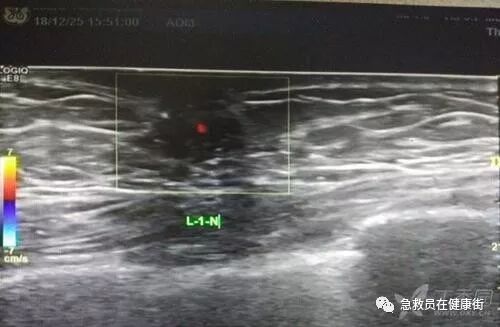

超声引导下乳房穿刺活检

乳房疾病日益增多,而乳房实质病变的良恶性、恶性肿瘤的分化及转移程度等直接关系到治疗方式的选择,因此,术前明确诊断尤为重要。超声引导下的乳房粗针及真空辅助旋切穿刺组织学活检因其定位准确、操作安全等优势得到广泛应用。

乳腺活检通常指乳腺肿块穿刺活检,常常在影像医学的引导下进行,以提高穿刺准确性。最常见的是在超声引导下进行。超声图像分辨率高,可以清楚看见活检针的位置和方向,在超声引导下进行的活检准确性高。